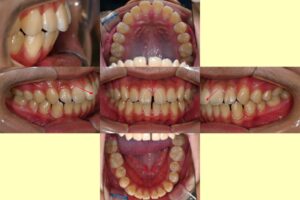

반갑습니다, 면목역 치과 글로리의 김정은 대표원장입니다. 교정이 필요한 순간들이 꽤 여럿 있습니다. 가지런하지 못한 치열을 가졌을 때도 있고, 때로는 맞지 않은 교합 관계의 문제, 그리고 뻐드러진 치열을 가질…

안녕하십니까, 망우역 치과 글로리 김정은 대표원장입니다. 『아름다운 미소에서 예쁜 치열은 필수 요소인데요.』 오늘은 전치부 재배열 후 아름다운 미소를 되찾은 사례의 치료 과정에 대해 설명해 드리도록 하겠습니다. 『1. 틀어진 앞니 교정』…

전체적으로 브라켓을 붙여 이를 이동시키는 치아교정은 비용뿐만 아니라 심리적 부담감도 따르기 마련입니다. 저희 글로리 신내동 치과 를 내원하시는 환자들께서도 마음은 먹고 오셨지만, 시작하기에 앞서 이런 걱정거리들을 얘기해 주시곤…